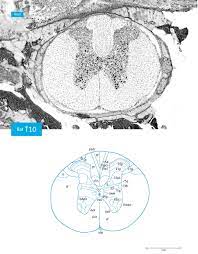

This pipeline is designed to generate an atlas of the spinal cord based on electron microscopy images. Protter is also linked from a number of tools and databases An rna seq atlas of gene expression. Protein structure refinement of il 1ra rat with chiron method download scientific diagram. A tool by matt gaidica.